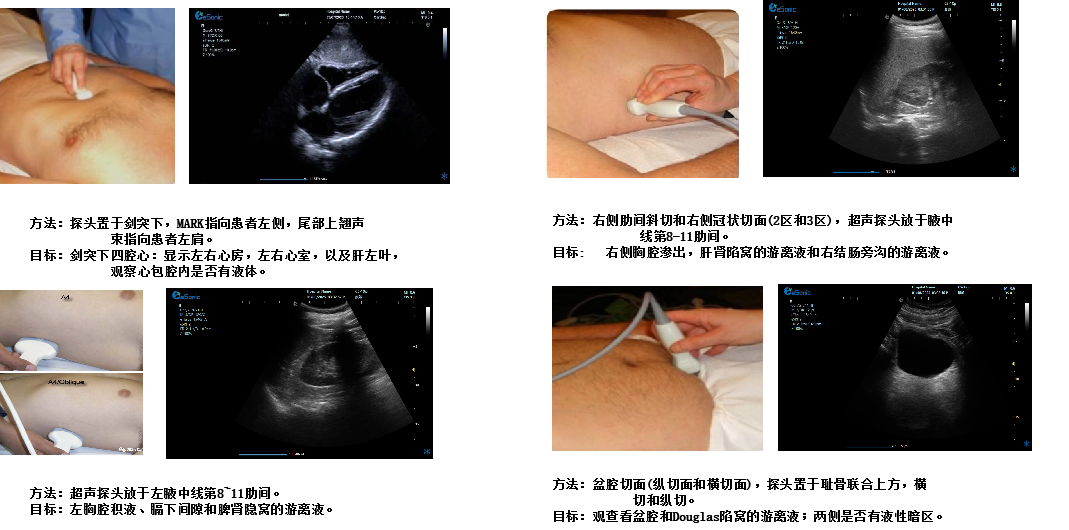

创伤评估FAST

image.png